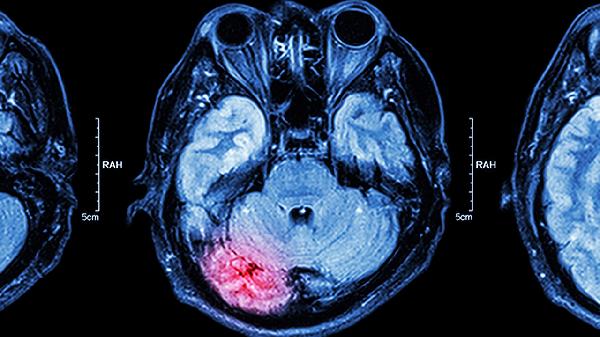

2、脑梗死

持续性脑供血不足可能导致局部脑组织坏死,形成脑梗死。患者会出现偏瘫、面瘫、吞咽困难等持续性神经功能缺损,头颅CT显示低密度病灶。发病机制涉及动脉闭塞、血流灌注不足,需紧急静脉溶栓或取栓治疗。恢复期可选用胞磷胆碱钠胶囊、丁苯酞软胶囊改善脑循环,配合银杏叶提取物片促进神经修复。